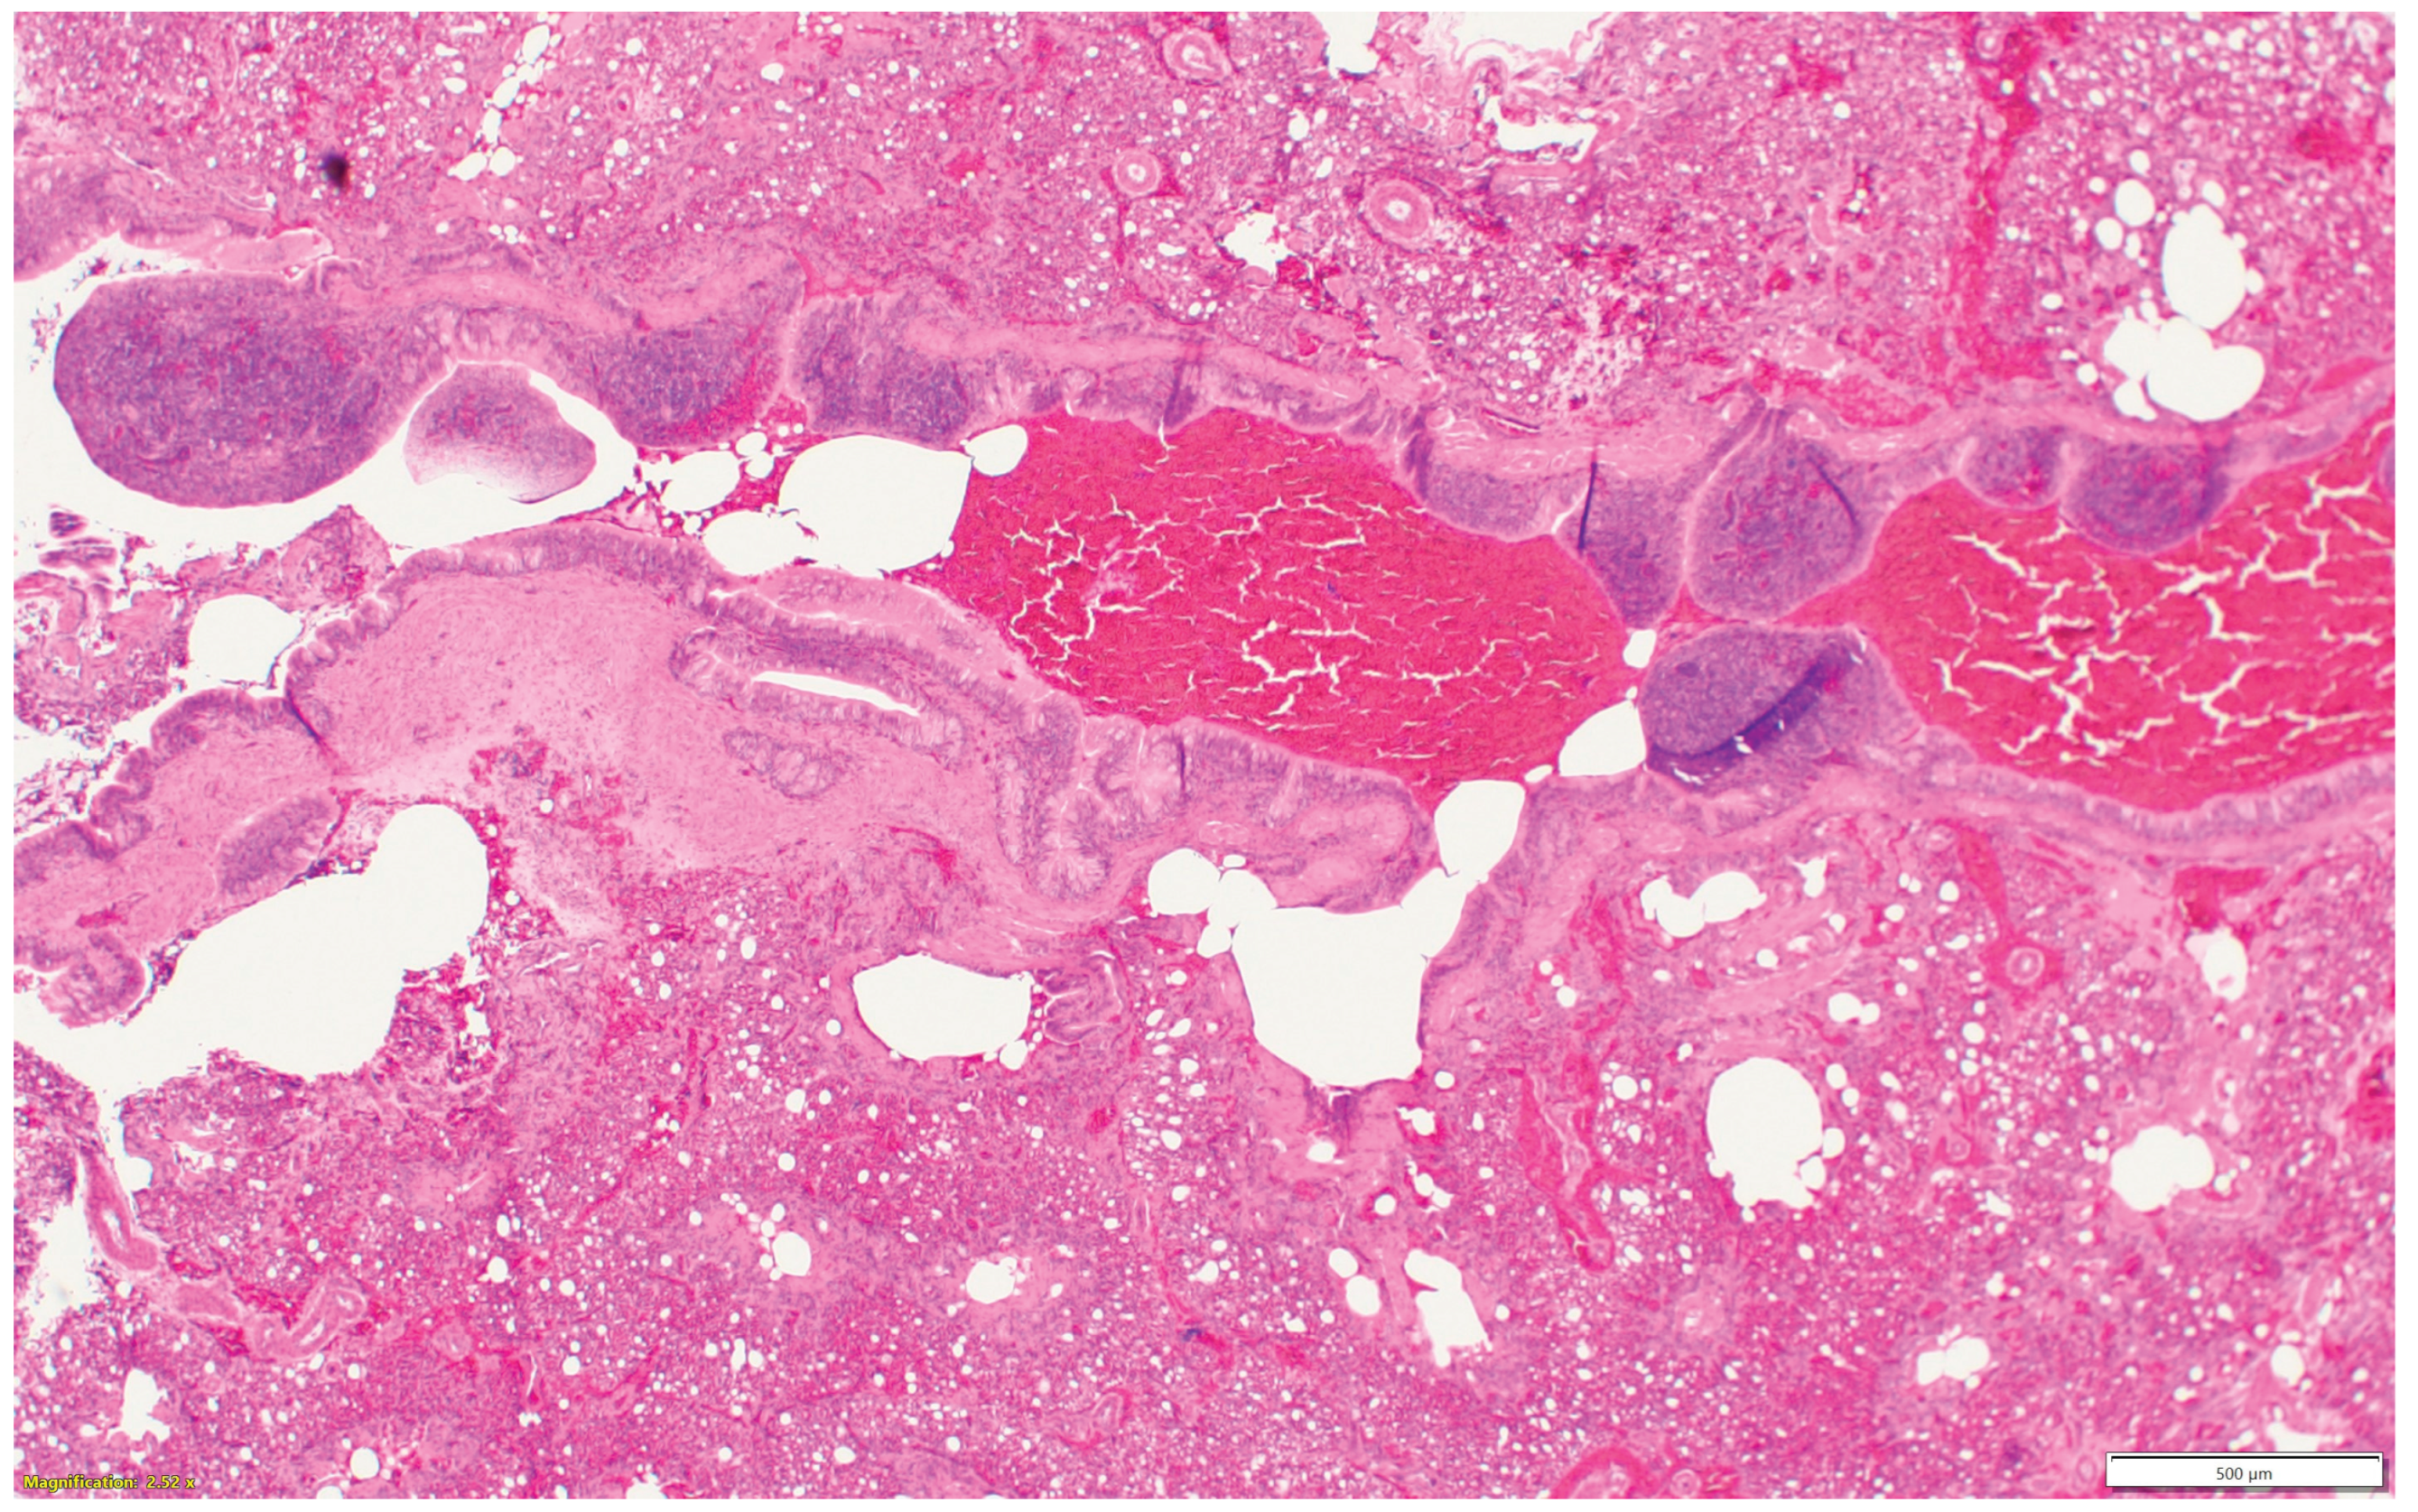

3.3. Turkeys inoculated with aMPV at 7 days of age showed higher lesion scores at 10 DPI compared with the non-infected control group. Sinus and eyelids were the main organs scoring points compared with other organs (Figure 4a).

3.4. Turkeys inoculated with low pathogenic avian influenza (LPAI-H4N6) at 7 days of age had also increased histologic lesion scores at 7 DPI compared with the non-infected control group. Sinus, lungs, eyelids, and trachea were orderly contributing to a higher total HRI (Figure 4b).